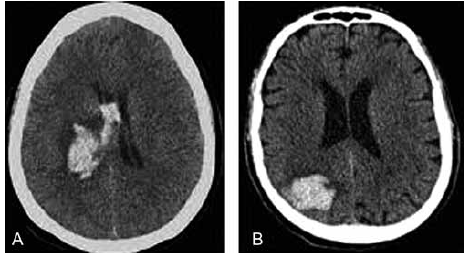

Um paciente de 65 anos é trazido ao pronto-socorro com início súbito de hemiparesia direita e afasia. A tomografia computadorizada (TC) de crânio encontra-se a seguir. O paciente tem histórico de hipertensão arterial sistêmica, mas não está em uso regular da medicação prescrita.

Qual abordagem terapêutica inicial é mais apropriada para esse caso?